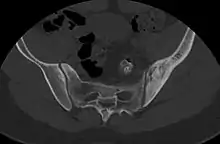

| Micrograph showing a large B cell lymphoma. Field stain. | |